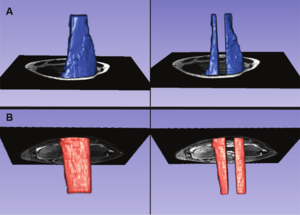

MRI-Only Based Radiotherapy Treatment Planning for the Rat Brain on a Small Animal Radiation Research Platform (SARRP)

Publication: PLoS One. 2015 Dec 3;10(12):e0143821. PMID: 26633302 | PDF Authors: Gutierrez S, Descamps B, Vanhove C. Institution: Medical Image and Signal Processing Group, Ghent University-iMinds Medical IT department, Ghent, Belgium. Background/Purpose: Computed tomography (CT) is the standard imaging modality in radiation therapy treatment planning (RTP). However, magnetic resonance (MR) imaging provides superior soft tissue contrast, increasing the precision of target volume selection. We present MR-only based RTP for a rat brain on a small animal radiation research platform (SARRP) using probabilistic voxel classification with multiple MR sequences. Six rat heads were imaged, each with one CT and five MR sequences. The MR sequences were: T1-weighted, T2-weighted, zero-echo time (ZTE), and two ultra-short echo time sequences with 20 μs (UTE1) and 2 ms (UTE2) echo times. CT data were manually segmented into air, soft tissue, and bone to obtain the RTP reference. Bias field corrected MR images were automatically segmented into the same tissue classes using a fuzzy c-means segmentation algorithm with multiple images as input. Similarities between segmented CT and automatic segmented MR (ASMR) images were evaluated using Dice coefficient. Three ASMR images with high similarity index were used for further RTP. Three beam arrangements were investigated. Dose distributions were compared by analysing dose volume histograms. The highest Dice coefficients were obtained for the ZTE-UTE2 combination and for the T1-UTE1-T2 combination when ZTE was unavailable. Both combinations, along with UTE1-UTE2, often used to generate ASMR images, were used for further RTP. Using 1 beam, MR based RTP underestimated the dose to be delivered to the target (range: 1.4%-7.6%). When more complex beam configurations were used, the calculated dose using the ZTE-UTE2 combination was the most accurate, with 0.7% deviation from CT, compared to 0.8% for T1-UTE1-T2 and 1.7% for UTE1-UTE2. The presented MR-only based workflow for RTP on a SARRP enables both accurate organ delineation and dose calculations using multiple MR sequences. This method can be useful in longitudinal studies where CT's cumulative radiation dose might contribute to the total dose. |

Illustration of a CB-CT and five MR images of the same animal. a) Coronal CB-CT image and (b)-(f) biased field corrected and masked coronal MR images using a T1-weighted (b), T2-weighted (c), ZTE (d), UTE1 (e) and UTE2 (f) sequence. All CB-CT images were first co-registered using 3D Slicer version 3.6.3 by rigid body transformations using normalized mutual information. |